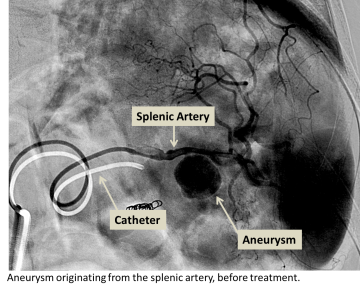

Splenic artery aneurysm before treatment